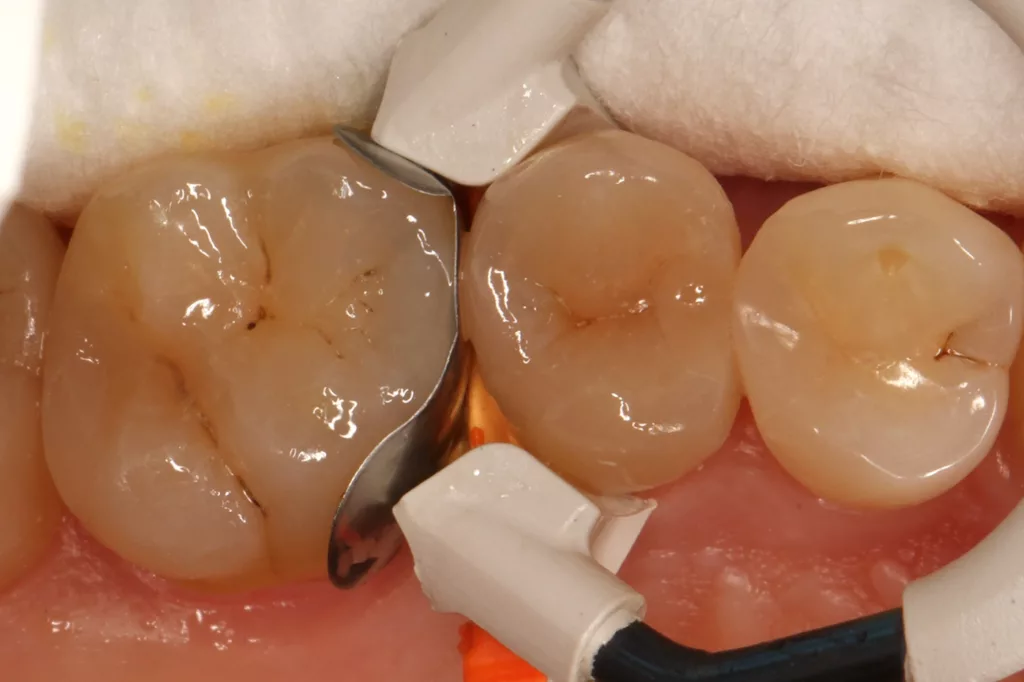

Fall 5: Versorgung einer okklusalen Kavität an einem unteren Molaren

Auch im Molarenbereich können Bulkflow-Materialien effektiv und ökonomisch eingesetzt werden, ohne Abstriche an der Ästhetik machen zu müssen, was der Fall des hier versorgten Zahnes 46 bei einer 22-jährigen Patientin zeigt. Die Abbildung 24 stellt die bereits präparierte und mit einem Einzelzahnkofferdam isolierte Kavität mit der Phosphorsäurekonditionierung der Schmelzränder (Gel Etchant, Kerr) dar. Die Entscheidung zur absoluten Trockenlegung fiel aufgrund der nicht so einfach kontrollierbaren Zunge und der vielen Schluckreflexe, was das Risiko einer ungewollten Speichelkontamination der Klebefläche unverhältnismäßig erhöhte.

Die Verwendung des Kofferdams ist generell eine sehr empfehlenswerte, aber keine zwingende Voraussetzung zur Etablierung einer suffizienten Kontaminationskontrolle [47,96]. Das bisher auch bereits verwendete Zwei-Schritt-Universaladhäsiv G2 Universal wurde hier in der selektiven Schmelzätztechnik angewendet, d.h., das Material arbeitet auf dem Dentin selbstkonditionierend (Abb. 25). Die bislang zu diesem innovativen Mehrflaschen-Universaladhäsiv publizierten Daten zeigen eine beeindruckende Performance, die den Vergleich mit sogenannten Goldstandards [98] wie einem Optibond FL nicht scheuen müssen [13,18,34,58,63,114,119,127,130]. Im nächsten Schritt wurden die einzelnen Höcker mit dem angenehm standfesten Flowable aufgebaut (Abb. 26). Die Abbildung 27 zeigt die komplett versorgte okklusale Kavität, die Abbildung 28 die Situation unmittelbar nach Ausarbeitung und Politur. Erneut beeindruckt die gute Farbadaptation.